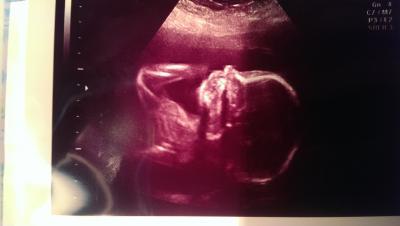

Hatte heute endlich wieder nen Ultraschall. Meinem süßen geht's super. Alles ist gut entwickelt. Er hat sich mit den Händen als im Gesicht rum gemacht und am Daumen genuckelt. Das einzigst doofe. Ich muss zum Spezialisten, da die plazenta zu tief liegt und eventuell auch vorm Ausgang. Hoffe das es sich nicht bestätigt. Dann müssten wir unsre fliterwochen nächsten Monat absagen, da man dann wohl nicht fliegen darf wegen Blutungen. Und natürlich hätte ich gerne diesmal ne normale Geburt. Noch hab ich Hoffnung.

Bild zu organscreening - Forum für August - Mamis

Super dass es dem baby gut geht. Drücke dir die Daumen dass die plazenta normal liegt. Süßes foto